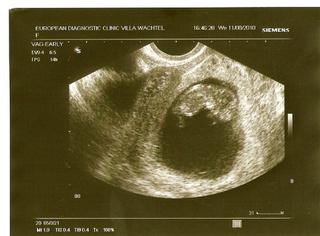

@l.u.c.i.e dopadla jsme dobře, vše ok 😵 , mimísek už má 3,5cm (crl) a už si tam hraje, mává nožičkama a ručičkama o 106 😀 🙂 . Ad zuby, někdo o nich vůbec neví, někdo má teploty a my máme něco speciálního, vždy jí rostou 2-3 naráz, takže mi 14 dní visí na noze a slintá jak bernardýn, pak se totálně pokaká a do pár hodin je zub venku (teda celej ne, celý zub roste většinou tak ten týden od proříznutí).